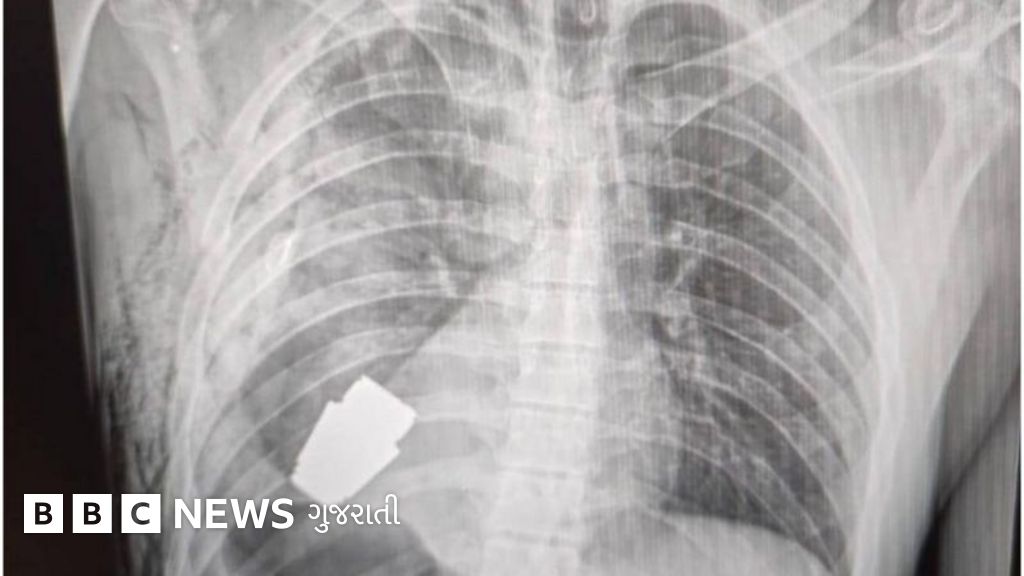

એ ઑપરેશન હતું, સૈનિકની છાતીમાં હૃદયની પાસે ફસાઈ ગયેલા એક જીવતો ગ્રેનેડ (હાથગોળો – બૉમ્બ)ને શરીરમાંથી દૂર કરવાનું.

યુક્રેનિયન સૈન્યના ડૉકટરોએ સફળતાપૂર્વક સર્જરી હાથ ધરી છે, જેમાં એક ઘાયલ સૈનિકની છાતીના પોલાણમાંથી જીવતો નાનો ગ્રેનેડ પાછો મેળવ્યો છે. આ અનોખી સર્જિકલ પ્રક્રિયાની જાણ યુક્રેનનાં નાયબ રક્ષામંત્રી હેન્ના મલિયર દ્વારા કરવામાં આવી હતી, જેમણે તેને "આશ્ચર્યથી ભરપૂર આનંદ" તરીકે વર્ણવ્યું હતું.

તેમણે ઉમેર્યું હતું કે બે લશ્કરી વિસ્ફોટક નિષ્ણાતોની દેખરેખ હેઠળ ગ્રેનેડને શરીરની બહાર કાઢી લેવામાં આવ્યો હતો. આ નિષ્ણાતોએ મેડિકલ સ્ટાફની સલામતી સુનિશ્ચિત કરી અને ગ્રેનેડમાં ભરેલા વિસ્ફોટકને બહાર જતા અટકાવવા માટે તેની સાથે કેવી રીતે કામ કરવું તેની સૂચનાઓ આપી હતી.

ઑપરેશન દરમિયાન મેડિકલ સ્ટાફ અને દર્દી સૈનિકની સલામતી માટે સર્જિકલ પ્રક્રિયામાં ફેરફાર કરવો પડ્યો હતો - ઇલેક્ટ્રોકૉએગ્યુલેશન, હૃદયની શસ્ત્રક્રિયા માટેની પ્રમાણભૂત પ્રક્રિયા જે રક્તસ્રાવને અટકાવે છે, તેનો ઉપયોગ ગ્રેનેડનો વિસ્ફોટ કરી દે તેવા ઇલેક્ટ્રિક પ્રવાહને ટાળવા માટે કરવામાં આવ્યો ન હતો.

રશિયન VOG ફ્રેગમેન્ટેશન ગ્રેનેડ જે સૈનિકના શરીરમાં મૂકવામાં આવ્યો હતો તેનો વ્યાસ 4 સેન્ટિમિટર (40 મિલિમિટર) છે અને તેનું વજન 250g હોય છે.